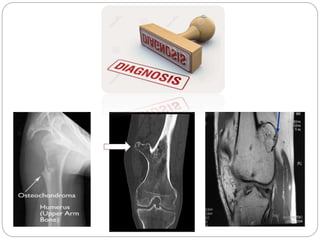

Osteochondroma is the most common bone tumor, forming cartilage-capped bony outgrowths on bones, typically during growth between ages 13-15. It occurs in the long bones of the legs, pelvis, or scapula. While most osteochondromas are asymptomatic, they can cause pain, nerve compression, or limit joint motion. Treatment involves surgery to remove symptomatic osteochondromas, while asymptomatic cases simply require follow up. Rapid growth, post-pubertal onset, or a cartilage cap over 2cm may indicate potential malignancy.